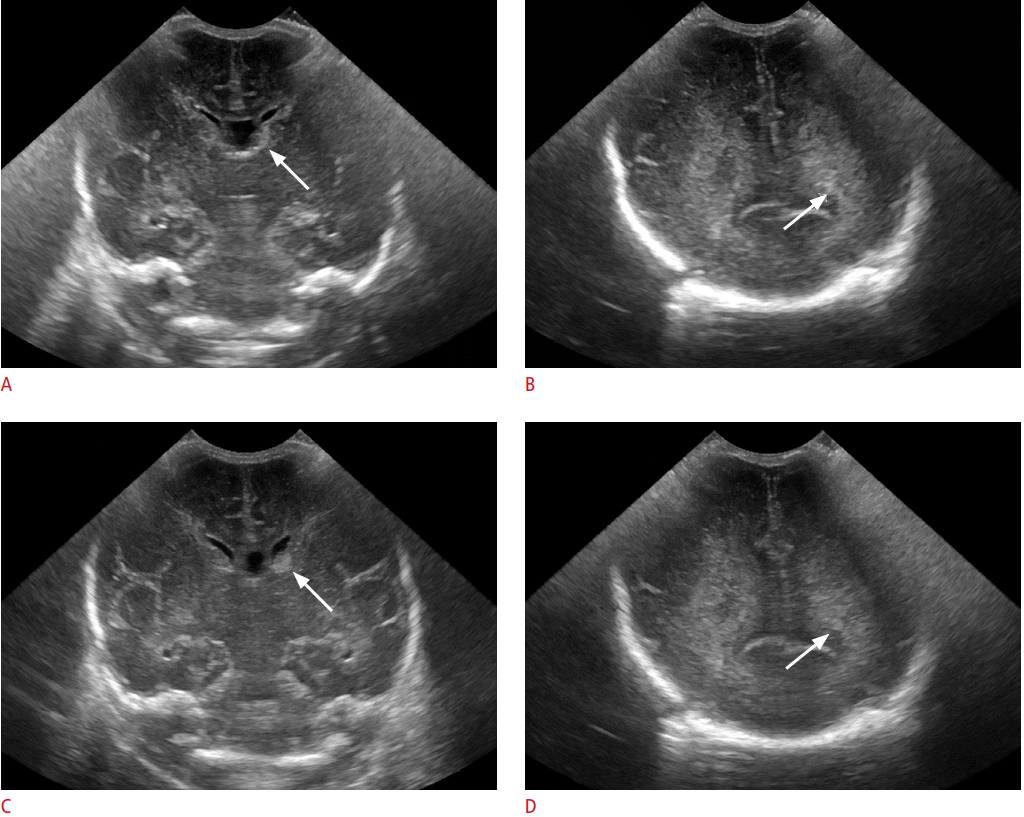

Siêu âm qua thóp là một kỹ thuật siêu âm được sử dụng để xem xét não và các mô mềm khác trong đầu của trẻ em. Kỹ thuật này cho phép các bác sĩ xem xét các cấu trúc bên trong đầu của trẻ em một cách chi tiết và không gây đau đớn cho trẻ.

Lợi ích của siêu âm qua thóp là nó cho phép các bác sĩ xem xét các cấu trúc bên trong đầu của trẻ em một cách chi tiết và không gây đau đớn cho trẻ. Tuy nhiên, nhược điểm của kỹ thuật này là nó không thể cung cấp cho các bác sĩ một hình ảnh toàn diện về não và các mô mềm khác trong đầu của trẻ.

- Không thể hiển thị được một số cấu trúc nhỏ trong não: Siêu âm sọ không thể hiển thị được các cấu trúc nhỏ hơn 2mm, do đó, nó không thể phát hiện được các khối u nhỏ hoặc các tổn thương nhỏ trong não.

- Không thể xuyên qua các cấu trúc xương: Siêu âm sọ không thể xuyên qua các cấu trúc xương, do đó, nó không thể hiển thị được các khu vực của não bị che bởi xương.